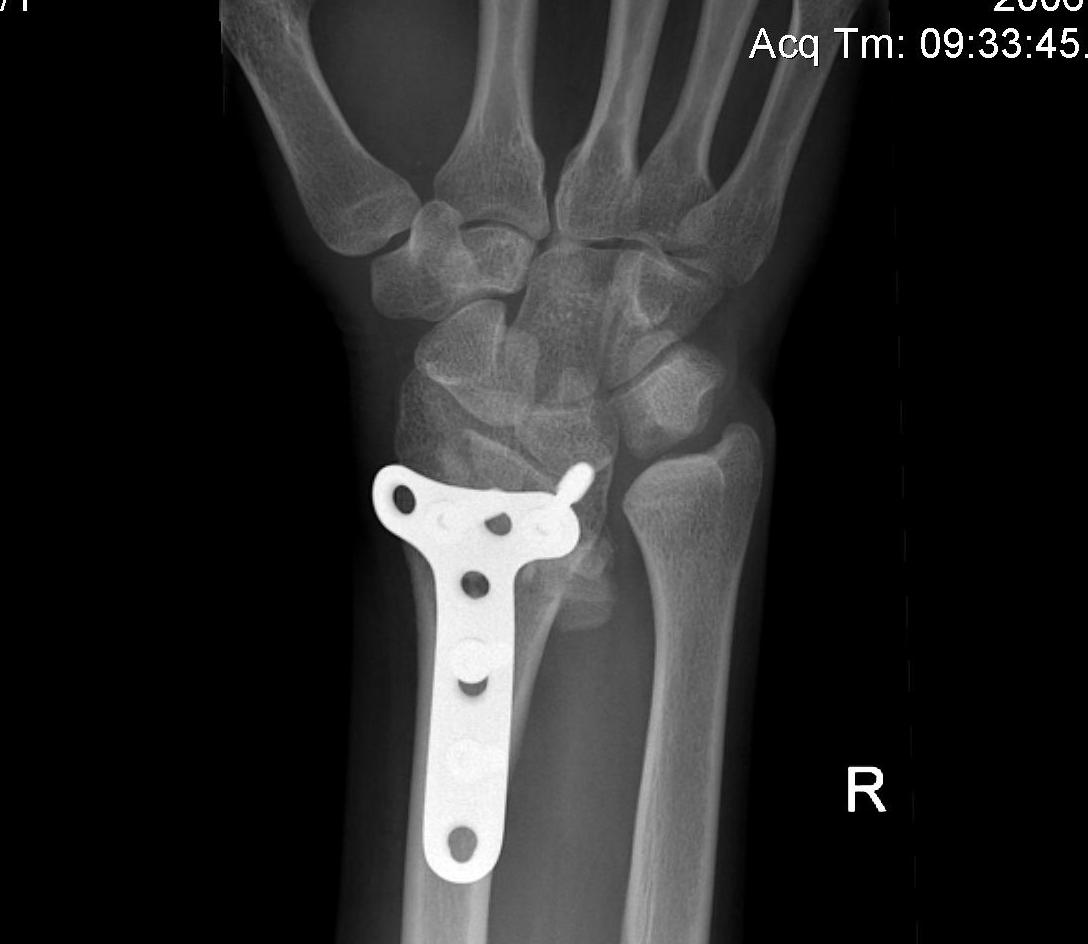

1. Excision Vicker's ligament + Epiphysiolysis of fused physis with fat graft

5. Opening Wedge Osteotomy